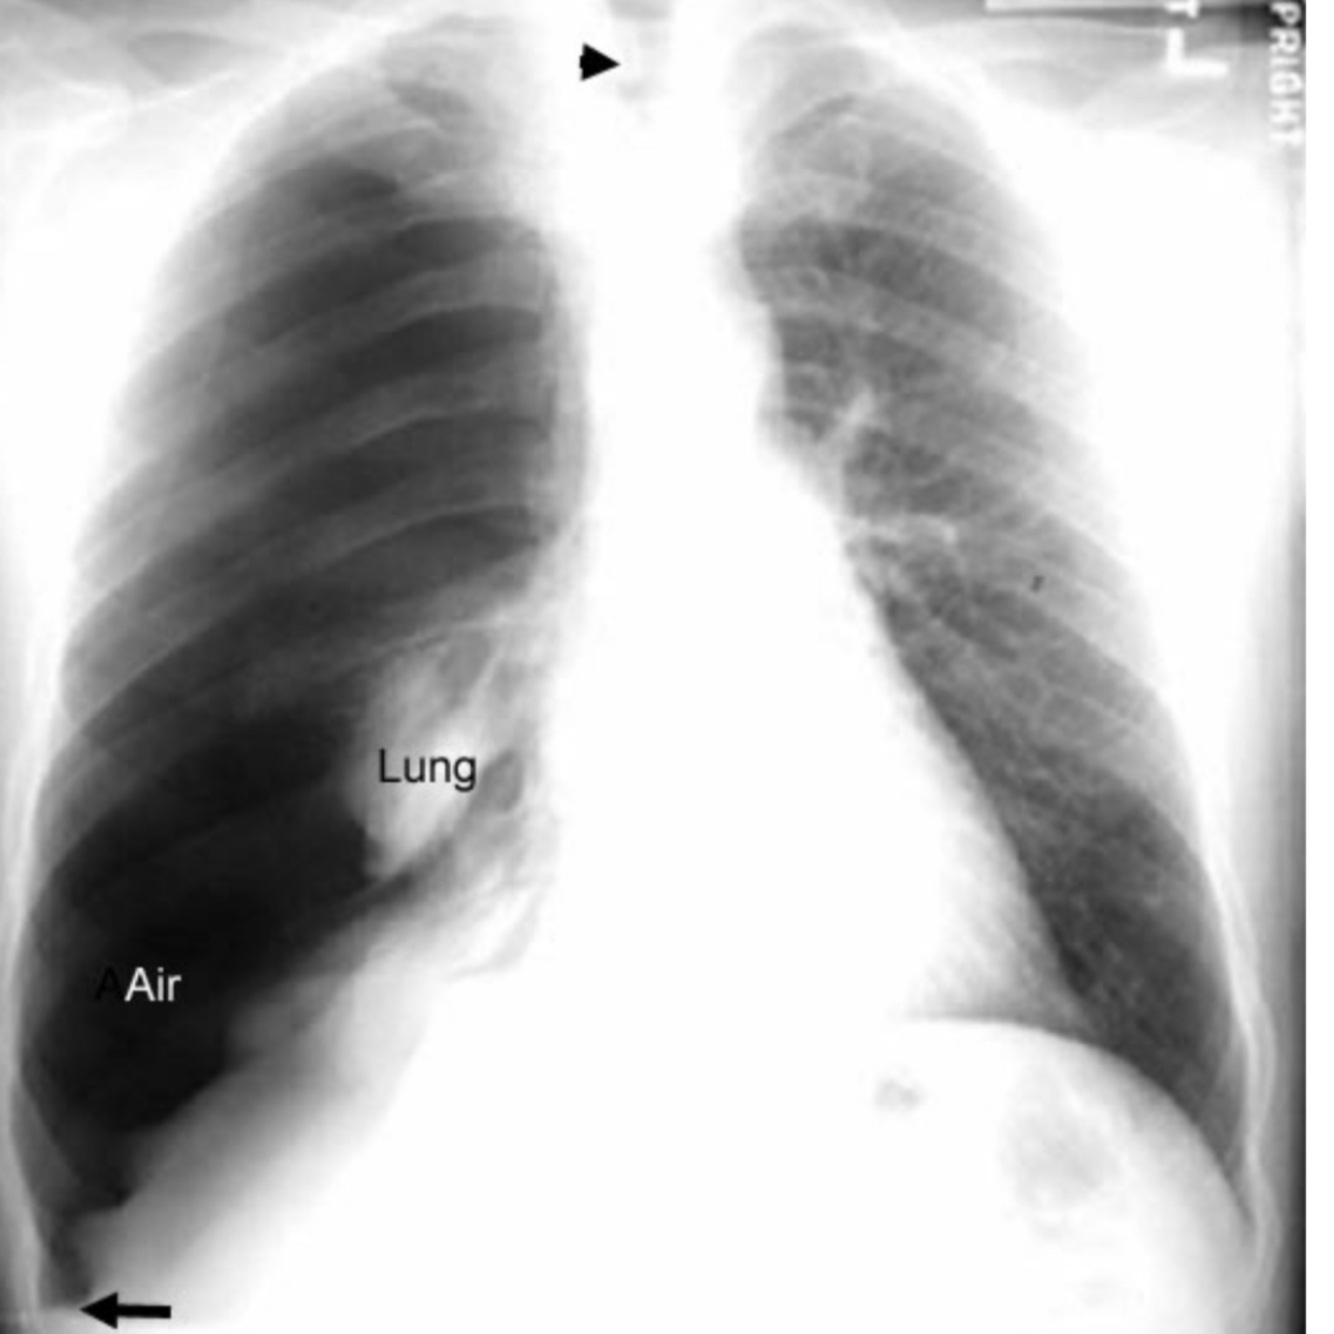

Signos de neumotórax

A

• Ruidos respiratorios ausentes

• Percusión resonante

• Vibraciones vocales disminuidas

• Ampliación disminuida